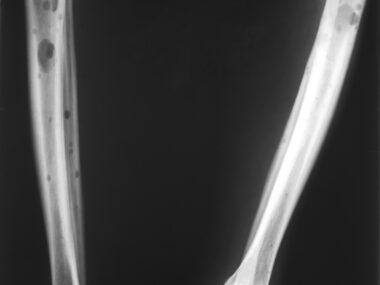

Myeloma is a rare blood cancer that begins in plasma cells, a type of white blood cell normally responsible for producing antibodies that help fight off infectious pathogens and other threats.

While myeloma treatment can drive the disease into remission, sometimes for long periods of time, the cancer will often come back after a few months or years, and additional treatments will be needed.